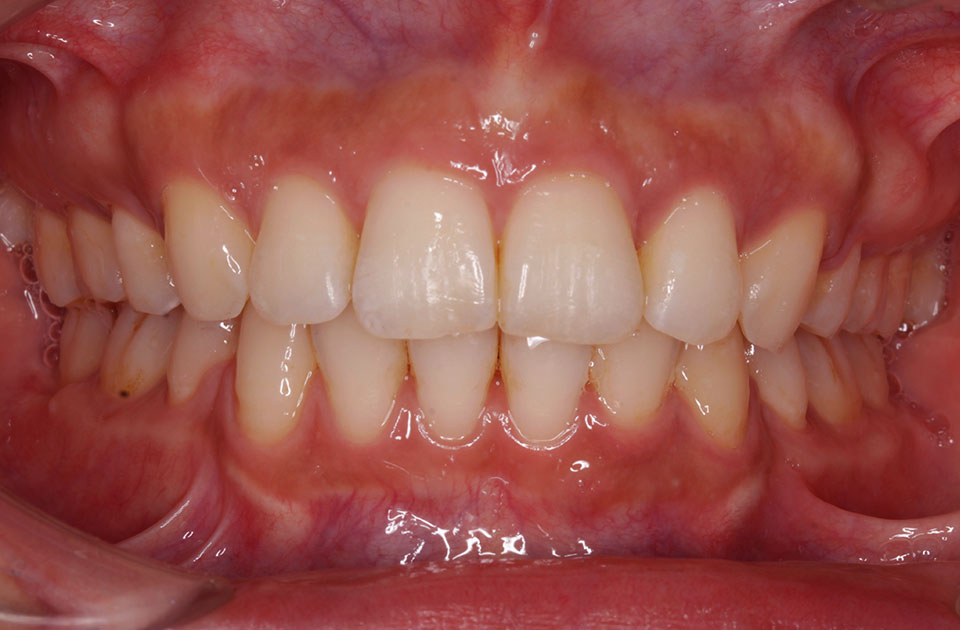

矯正後

矯正前 正面

矯正後 正面